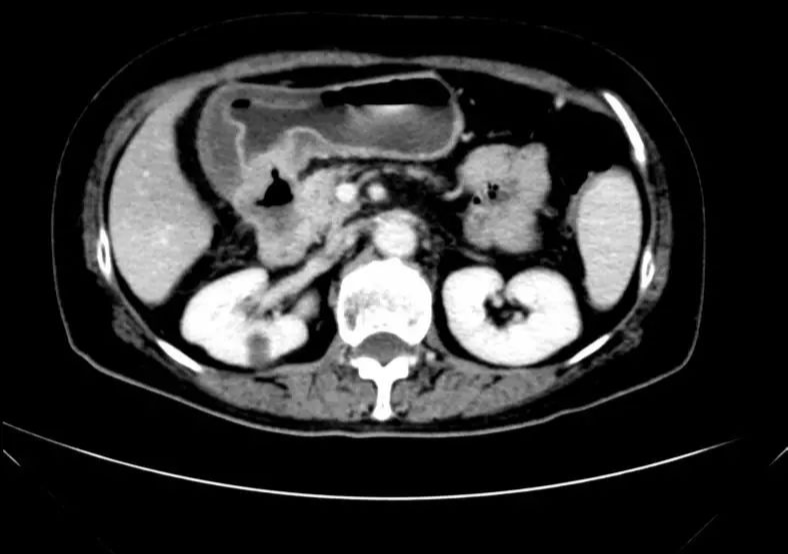

CT-T

CT-H1

影像学检查结果评估:cPD。